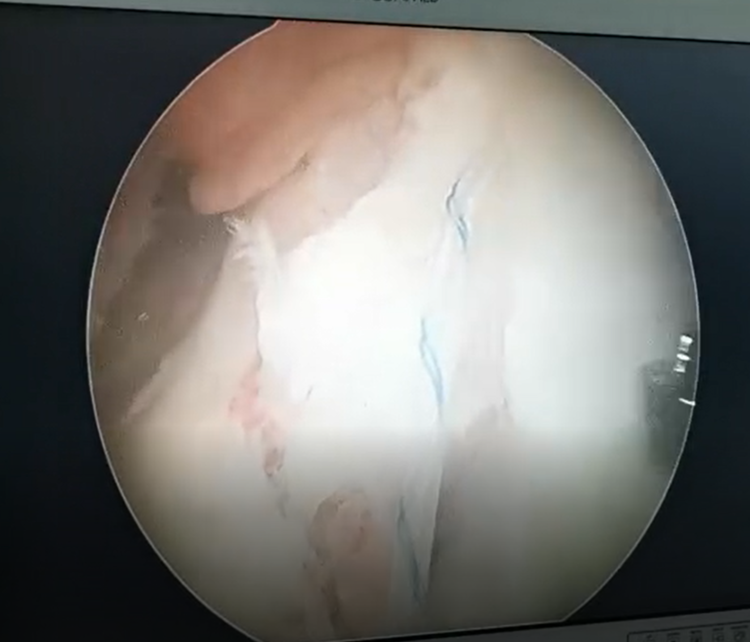

镜下探查见,ACL胫骨止点撕脱骨折,边缘伴少量血痂,内侧胫骨平台骨折,关节面软骨劈裂,无塌陷。

关节镜下,PDS-Ⅱ缝线牵引高强度缝线编织缝合ACL。

三角形缝合固定后,牵拉高强度线见撕脱骨折复位,稳定。

前抽屉状态下,肩关节外排钉于胫骨骨道挤压固定缝线。